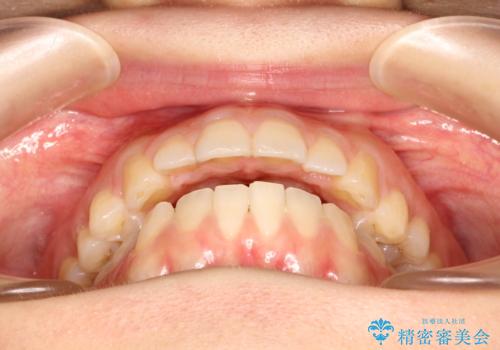

上下の前歯が当たらない インビザラインによる開咬の矯正治療

- 上下の前歯の間に隙間があるとのことで来院されました。

開咬とよばれる、奥歯しか上下の歯が接触していない状態でした。

使用時間を守っていただけたので、比較的スムーズに矯正を終了することができました。

前歯で物が咬み切れるようになり、喜んでいただけました。

舌の使い方が上手ではなかったので、治療と同時に舌のトレーニングを行いました。